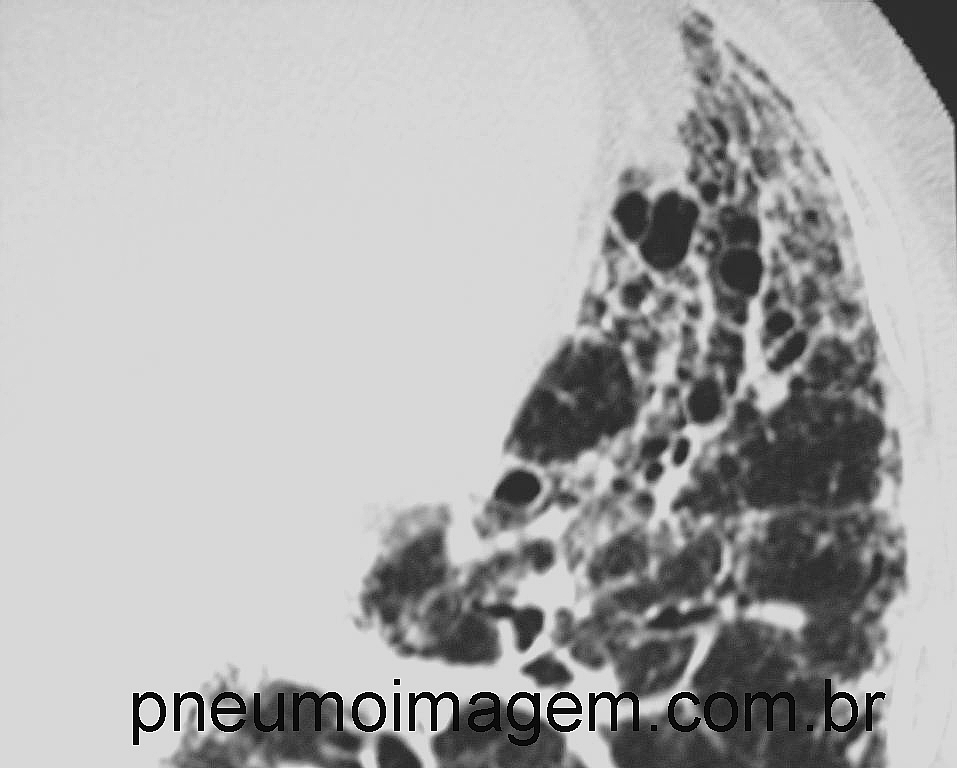

Nos fibroblastos da FPI, nintedanib reduziu a expressão de colágeno I e V, fibronectina e FKBP10, e atenuou a secreção de colágeno I e III. Pirfenidona também regulou o Colágeno V para baixo, mas com efeitos menos pronunciados. Em geral, os efeitos foram semelhantes nos fibroblastos saudáveis. Para ambos os medicamentos, a microscopia eletrônica das culturas de fibroblastos na FPI revelou menos e menores fibras de colágeno em comparação com controles não tratados. Finalmente, ambos os medicamentos retardaram de maneira dose-dependente a formação de fibras de colágeno purificado I.

Em resumo, ambas as drogas atuam em níveis regulatórios importantes na síntese e processamento do colágeno. Nintedanib foi mais eficaz na regulação negativa da expressão de genes profibróticos e na secreção de colágeno. Importante notar que ambas as drogas inibiram a formação de fibras de colágeno I e causaram uma redução e uma alteração dessas fibrasno, o que representa um novo mecanismo de ação para essas drogas.